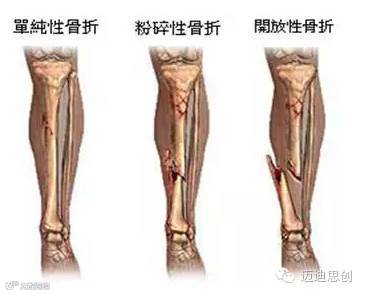

1、外伤骨头——粗看X光片、细看CT

各种外伤,如果怀疑伤到了骨头,优先选择X光照片,检查结果快速易得。若要进一步观察,可以选择CT。超声、核磁对于骨皮髓质等看不大清,一般不选择。